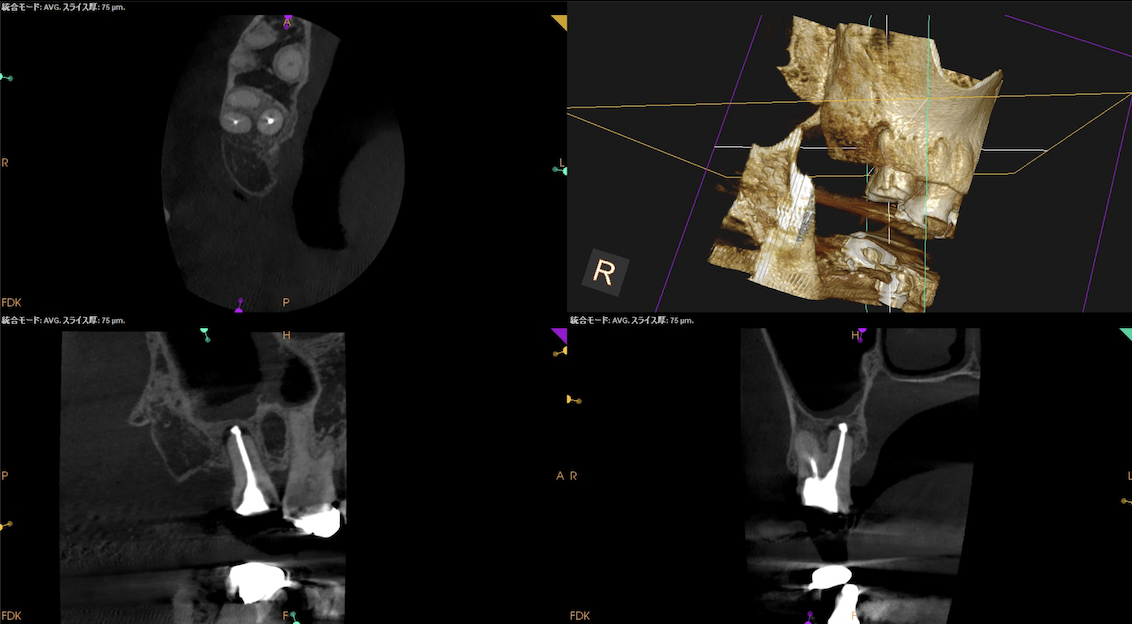

根管充填後にPA, CBCTを撮影した。

DB

P

問題はないだろう。